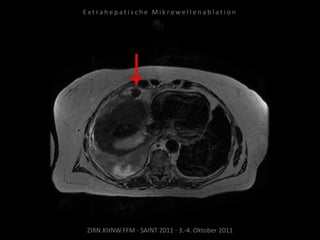

Ausgangsbildgebung:

CT vom 21.12.2009

Bildgebung vor MWA:

CT vom 14.07.2010

Metastase lateral der linken Niere

nahe Colon descendens progredient.